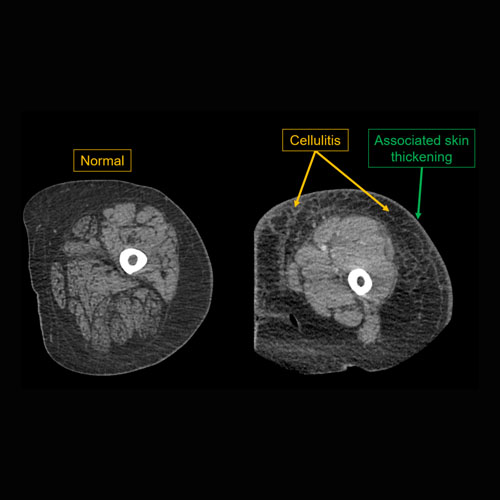

Section 1 Submit Findings CB1118 Findings Limitations There is patient motion or other limitations. Yes No Skin/Hypodermis There is edema or hyperenhancement. Yes No There is soft tissue ulceration or sinus tract. Yes No There is gas or foreign body. Yes No There is confluent hypoenhancement to suggest phlegmon, suppuration, abscess, or drainable fluid collection. Yes No Investing/Intermuscular Fascia There is edema, thickening, or hyperenhancement. Yes No There is hypoenhancement or gas along the fascia. Yes No There is bulging of the fascia. Yes No Muscles There is edema or hyperenhancement. Yes No There is hypoenhancement, lack of enhancement, or organized fluid collection. Yes No There is fatty atrophy. Yes No Bones There are fractures. Yes No There is periosteal reaction, osseous destruction, or focal demineralization to suggest osteomyelitis. Yes No There is cloaca, sequestrum, or involucrum. Yes No There is a subperiosteal or intra-osseous abscess. Yes No Visualized Joints There is a joint effusion. Yes No There is malalignment, degenerative changes, or other gross internal derangement. Yes No Miscellaneous There is tenosynovitis. Yes No Major visualized vascular structures are abnormal. Yes No Major visualized nerves are abnormal. Yes No